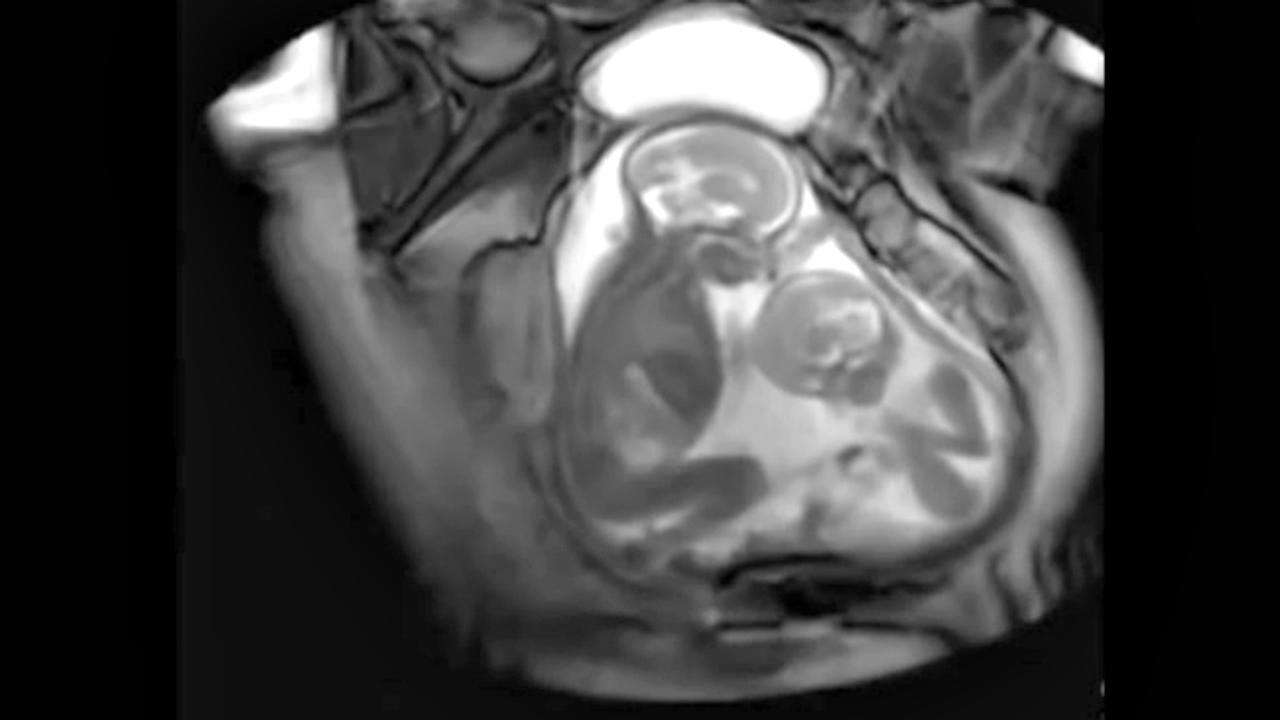

Liputan6.com, London - Sepasang bayi kembar terekam sedang 'berkelahi' di dalam rahim ibu mereka, saat pemindaian proses MRI di sebuah rumah sakit di London, Inggris. Dalam rekaman tersebut, terlihat keduanya saling tendang.

Berikut ini detik-detik saat kedua jabang bayi kembar itu saling tendang: